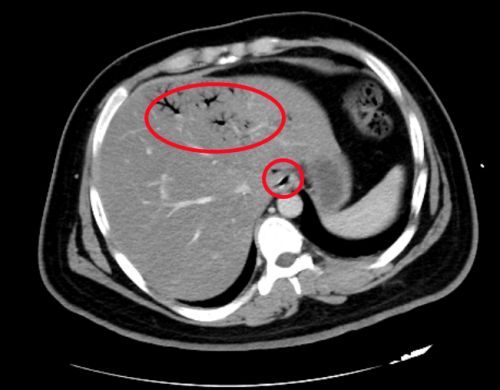

ct显示,肝脏、门静脉、肠壁内都有明显积气(红圈内)。

进入急诊三科抢救室时,小刘已经神志浅昏迷,呼吸急促,脉搏高达145/分,血压低至休克,快速血糖检测高到“爆表”,只得抽血测血糖,结果显示为123.10mmol/L,超出正常值20多倍!此外,感染指标明显升高;腹部 CT显示:左肝静脉、门静脉、肠系膜静脉及小肠壁积气明显,考虑小肠坏死,随即转入急诊重症病房(EICU)。

“门静脉和肠系膜静脉等出现积气是因为产气细菌进入血液,这种情况在影像学上被称为‘死神之征’,死亡率高达50%”,湖南省人民医院急诊三科主任张兴文主任医师表示,小刘由于不良生活方式导致体重超标,并患上糖尿病,在此之前一直没有规范治疗和改变不良生活方式,这次因为肠道菌群失调、移位出现肠源性感染,引发感染性休克,最终导致严重的糖尿病酮症酸中毒(DKA),危及生命。